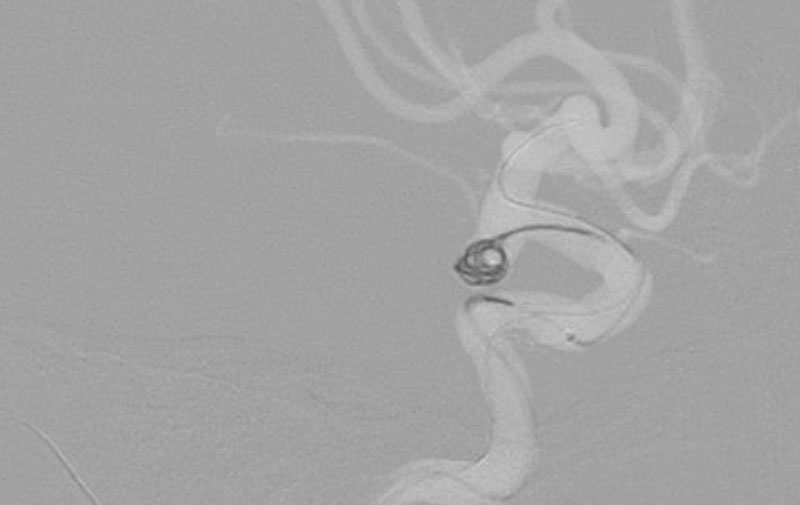

No.1596 手術後